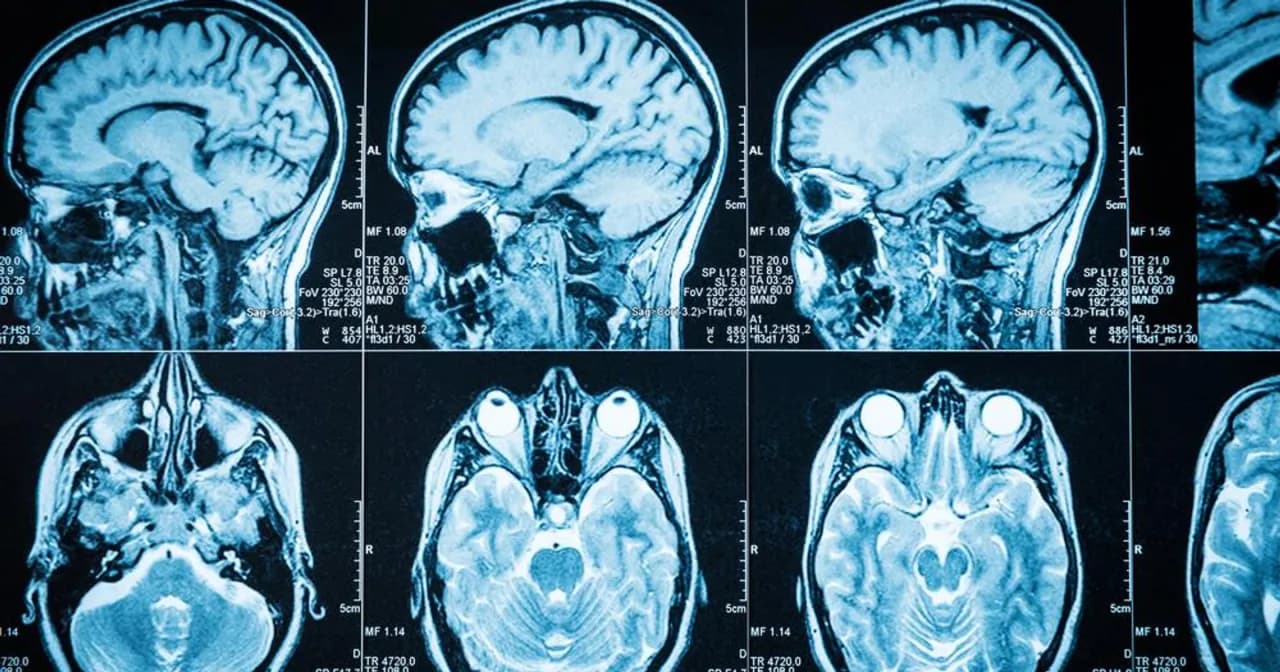

Guz mózgu to poważne schorzenie, które może prowadzić do różnorodnych objawów psychicznych. Objawy te często są pierwszymi sygnałami choroby, które mogą być mylone z codziennym stresem lub zmęczeniem. Warto zrozumieć, jak lokalizacja guza w mózgu wpływa na zachowanie i samopoczucie pacjenta. Wiele osób nie zdaje sobie sprawy, że zmiany w osobowości, problemy z pamięcią czy zaburzenia nastroju mogą być związane z obecnością guza. Dlatego tak ważne jest, aby być świadomym tych symptomów i reagować na nie odpowiednio wcześnie.

Guz mózgu może prowadzić do różnorodnych objawów psychicznych, które często są pierwszymi sygnałami choroby. Wiele osób nie zdaje sobie sprawy, że zmiany w zachowaniu mogą być związane z obecnością guza. Wczesne rozpoznanie tych symptomów jest kluczowe, ponieważ może prowadzić do szybszej diagnozy i leczenia. Warto zwrócić uwagę na to, jak lokalizacja guza w mózgu wpływa na psychikę pacjenta oraz jakie zmiany mogą wystąpić.Objawy psychiczne mogą być subtelne i często są mylone z normalnym stresem lub zmęczeniem. Dlatego tak ważne jest, aby być czujnym na wszelkie zmiany w osobowości, zachowaniu czy nastroju. W przypadku wystąpienia poważnych zaburzeń u osoby, która wcześniej nie miała takich problemów, należy rozważyć konsultację z lekarzem. Wczesne wykrycie problemu psychicznego może znacznie poprawić jakość życia pacjenta oraz jego bliskich.